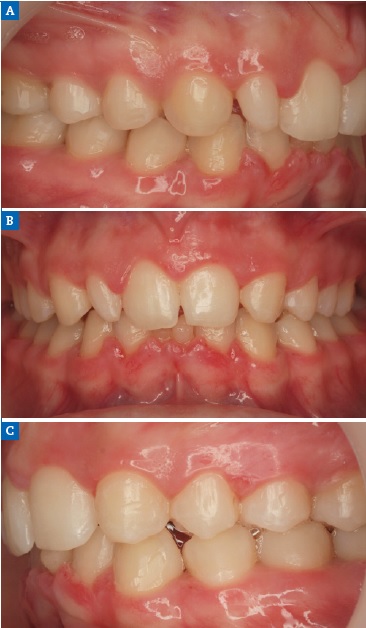

Figure 2 Case 1: Intraoral views of the (A) right, (B) frontal, and (C) left aspects before orthodontic treatment.

Orthodontic treatment involving space closure was performed. After golden proportion (Figure 4) and Bolton’s anterior analysis, the presence of a 77.7% dental discrepancy in the anterior relation with mandibular excess was confirmed (14, 13, 11, 21, 23, 24, / 33, 32, 31, 41, 42, 43). Due to the agenesis of the maxillary lateral incisors and the need to perform esthetic restorations in the upper arch to improve smile harmony, a similar Bolton anterior discrepancy of 76% was obtained after restorations. After orthodontic treatment, shade selection was accomplished using a Vita Shade Guide (Figure 5), and dental bleaching was performed. Afterward, according to clinical findings and with careful consideration of all treatment options available for rehabilitation, it was decided that the maxillary canines and first premolars would be additively remodeled to the shape of lateral incisors and canines, respectively, using direct composite (Figure 6), which provides advantages in symmetrical cases.

Figure 6 Case 1: Maxillary canines and first premolars additively remodeled to the shape of lateral incisors and canines, respectively, using direct composite ((A) right, (B) frontal, and (C) left aspects).